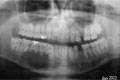

Paciente feminina de 19 anos, branca, em bom estado geral. Refere abaulamento com crescimento lento e progressivo há 1 ano, na região dos dentes 12 e13, assintomático. Rx- área radiolúcida, bem delimitada, atingindo 2cm no maior diâmetro

Paciente do gênero masculino, 29 anos de idade, apresenta lesão detectada há 4 anos e tratada inicialmente com descompressão.